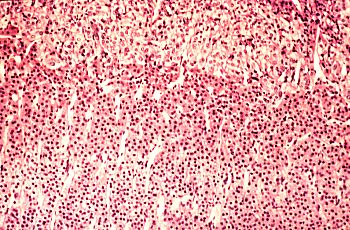

Fig 56-007 |